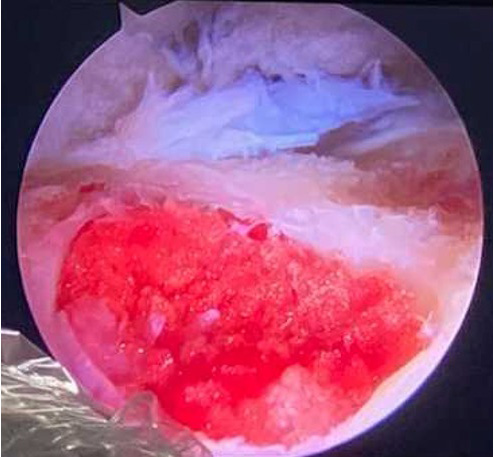

Beyond the image : what does it look like in reality ?

➡️ FAI resection

Pitt’s pit is found at cam/neck junction at 3 o’clock